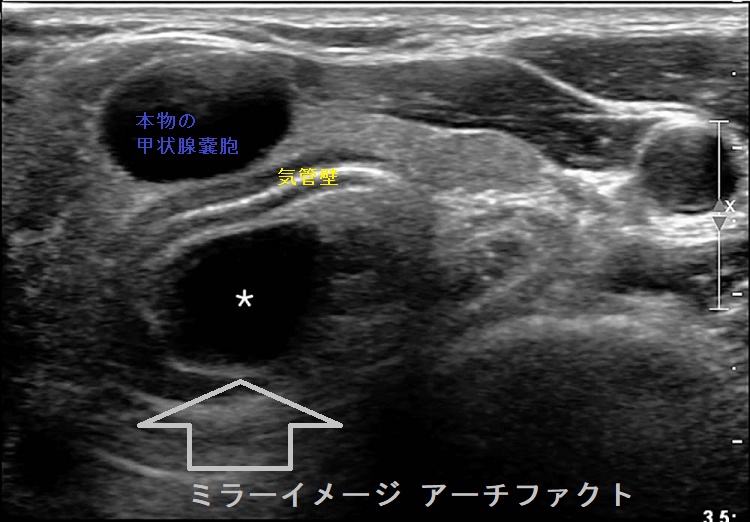

気管に近接する甲状腺嚢胞(のう胞)では、超音波(エコー)検査においてミラーイメージ アーチファクトを生じるケースがあります。過度に収縮して超音波(エコー)を反射しやすくなった気管壁から跳ね返ってきた反射波が、周囲の構造物に当たり、再度気管に向かう2重の反射波が原因(鏡面反射の原理)。この現象により、2重の反射波が時間差を置いて帰ってくるため、気管壁の内側(気管内腔)に同じエコー像が現れます。

もちろん、現実には存在しないアーチファクトなので、頸部CTには写りません。穿刺排液で甲状腺嚢胞(のう胞)が縮小すればミラーイメージも縮小します。

[Radiol Case Rep. 2018 Feb 9;13(2):408-410.]